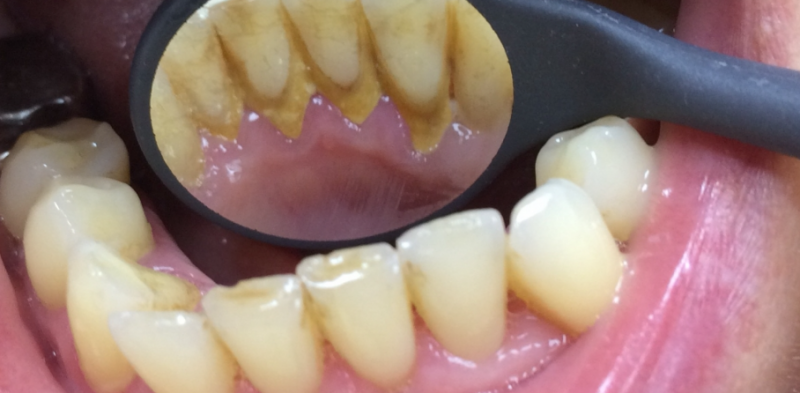

На странице представлено портфолио стоматологий Санкт-Петербурга с работами до и после профессиональной чистки зубов. В нашем портфолио собраны разные клинические случаи: от удаления незначительного налета до снятия массивного поддесневого камня. Здесь вы можете увидеть, как возвращается естественный цвет и внешний вид зубов после процедуры. Изучите результаты до и после чистки зубов, чтобы увидеть реальный эффект и выбрать клинику в Санкт-Петербурге, где профессиональная гигиена поможет вернуть зубам здоровый вид.

Профгигиена